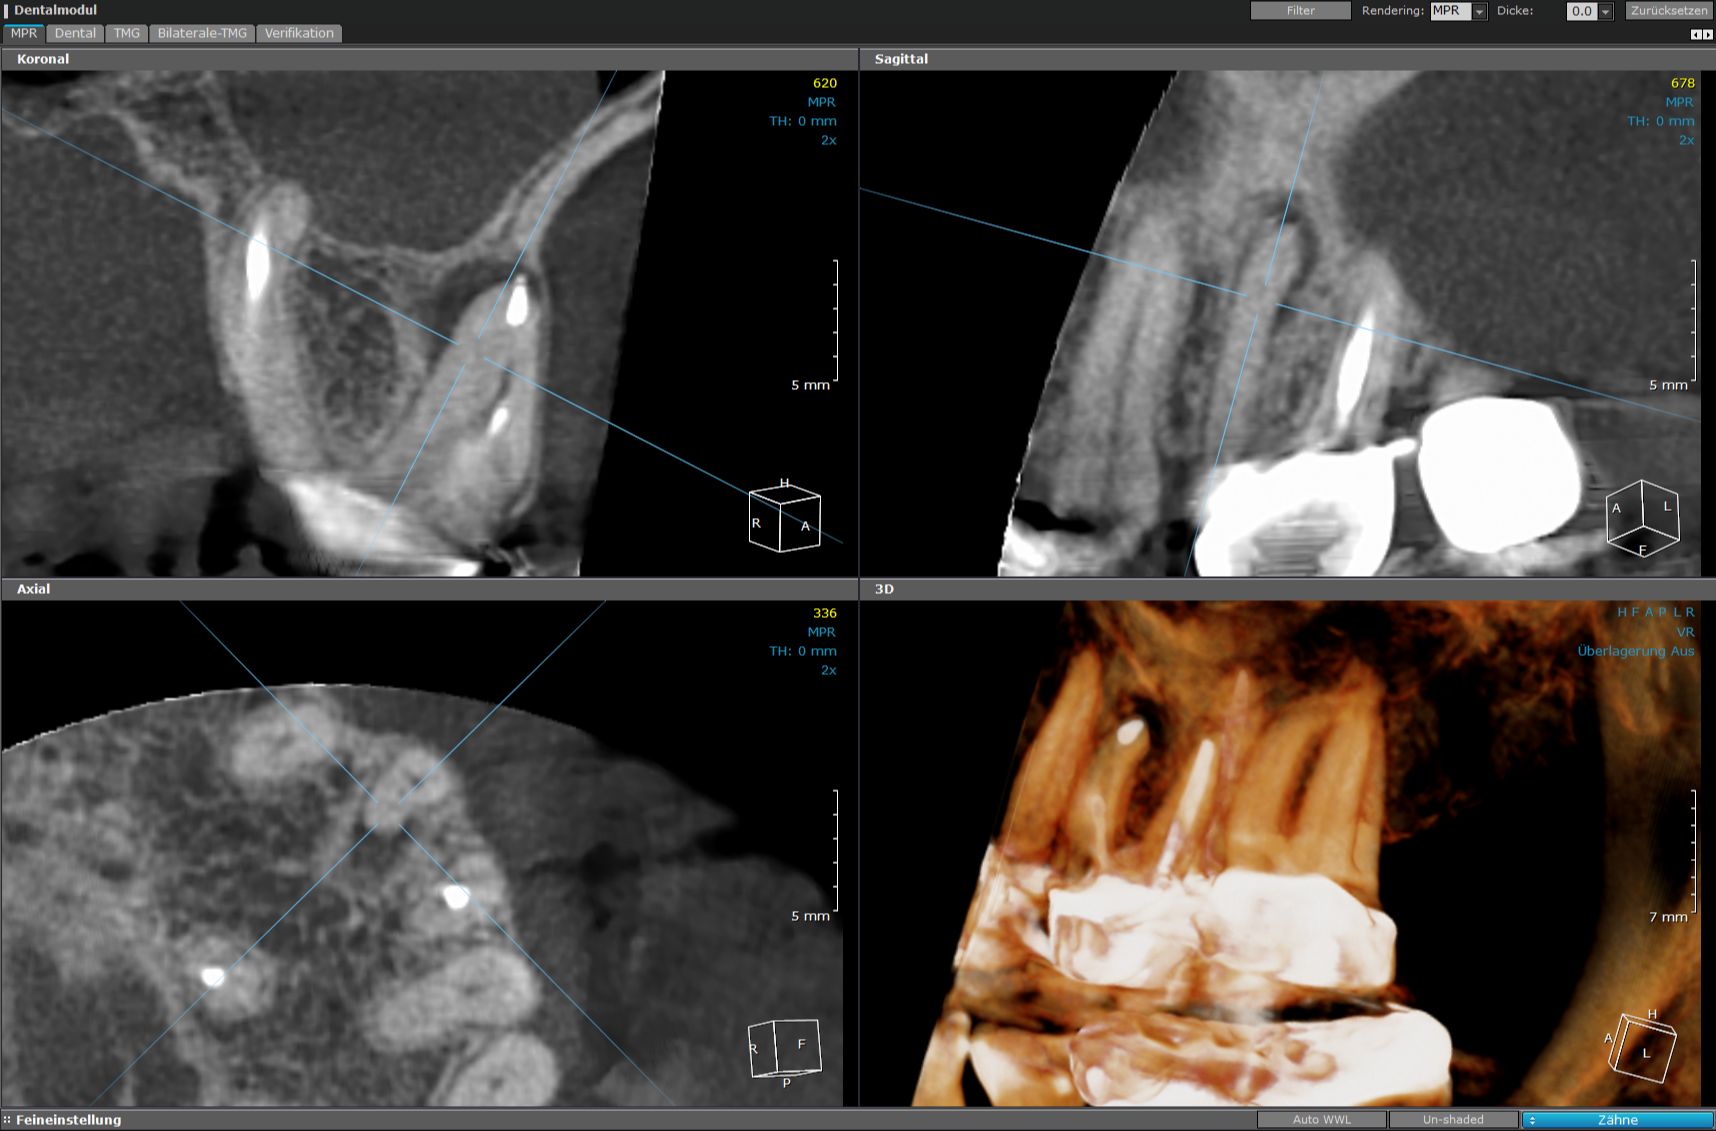

Vorteile der 3D-Röntgentechnik in der Endodontologie

In der Endodontologie – das ist die Lehre von der Behandlung des Zahninneren – ist unser 3D-Röntgengerät sehr wertvoll. Für das geübte Auge des Zahnarztes macht es die feinen Strukturen des Zahninneren erkennbar. Es zeigt exakt die Anzahl, Lage und Länge der Wurzeln, ihren Verlauf und Zustand. Am Bildschirm lassen sich die berechneten Aufnahmen um alle Achsen drehen.

Hier gilt ganz besonders: Nur was ich sehe, kann ich auch (erfolgreich) behandeln.

- Hohe Auflösung (0,1 mm) für detailreiche Darstellung macht kleinste Strukturen sichtbar

- 80% geringere Strahlendosis gegenüber herkömmlichen zweidimensionalen Röntgen

- Die dreidimensionale Darstellung zeigt auch Strukturen, die im zweidimensionalen Röntgenbild verdeckt werden